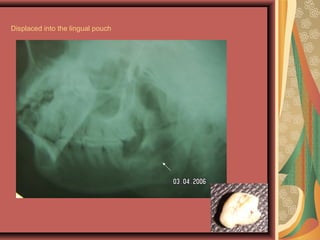

Displaced tooth – lingual pouch/periosteum, lateral

pharyngeal space, air way , GI( antrum, infratemporal

pouch in upper)

Displaced into the lingual pouch